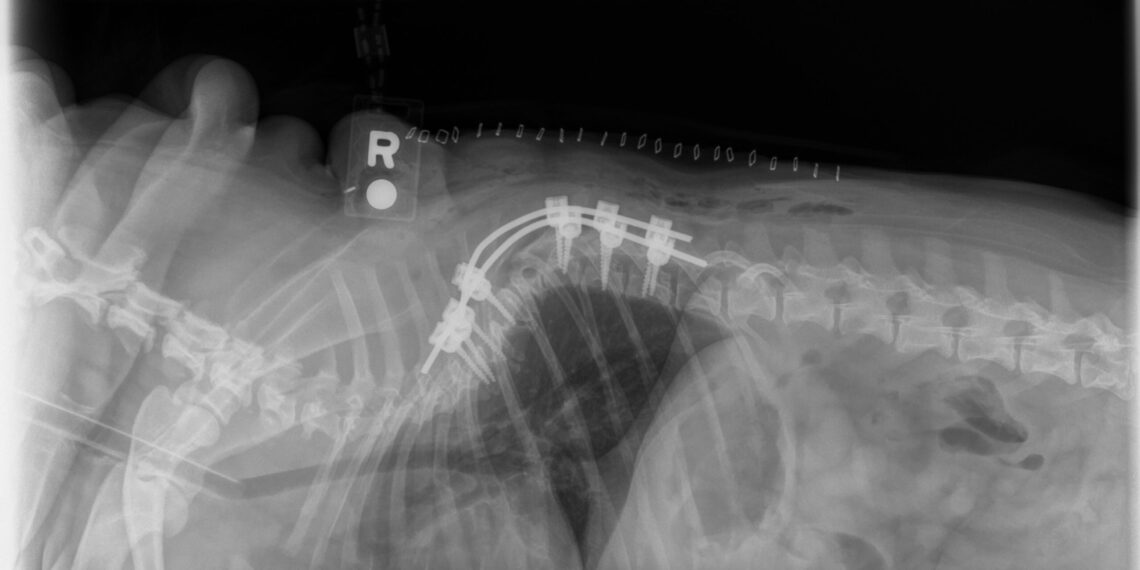

Canine Vertebral Stabilization

Specialist-Level Lectures & Roundtables: Topics include intracranial surgery, skull reconstruction, minimally invasive neurosurgical techniques, spinal biomechanics, implant decision-making, comparative neurosurgery strategies, and advances in lumbosacral surgery.